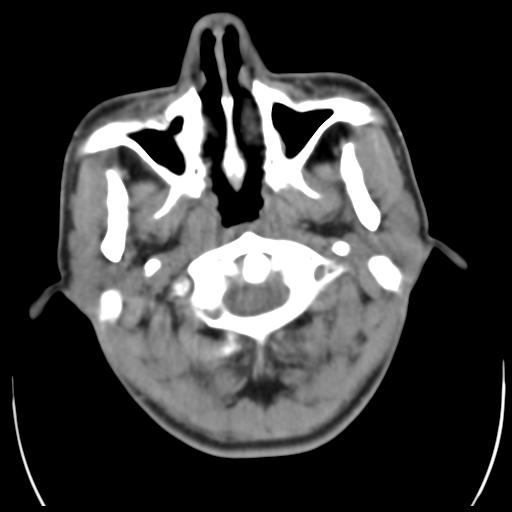

35m 鼻子时不时流血,头及右侧面部痛,颈部淋巴结未见明显大

这个东西大家仔细看看呀

考虑鼻咽癌侵犯颅底并突入右侧鼻腔;双侧中耳乳突炎。

鼻咽血管纤维瘤?

考虑中线肉芽肿(鼻硬结病),次之tb或真菌感染性肉芽肿,病变形态不像肿瘤,建议增强及活检。